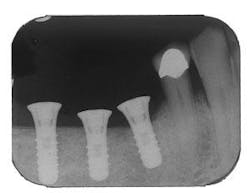

Figure 5 - Placement of three ITI implants

Figure 10 - Restored implants